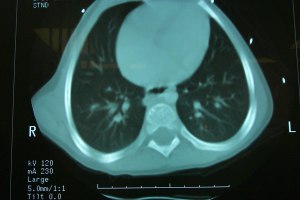

Published at 300 × 200 in Chapter 30. Remote Locations